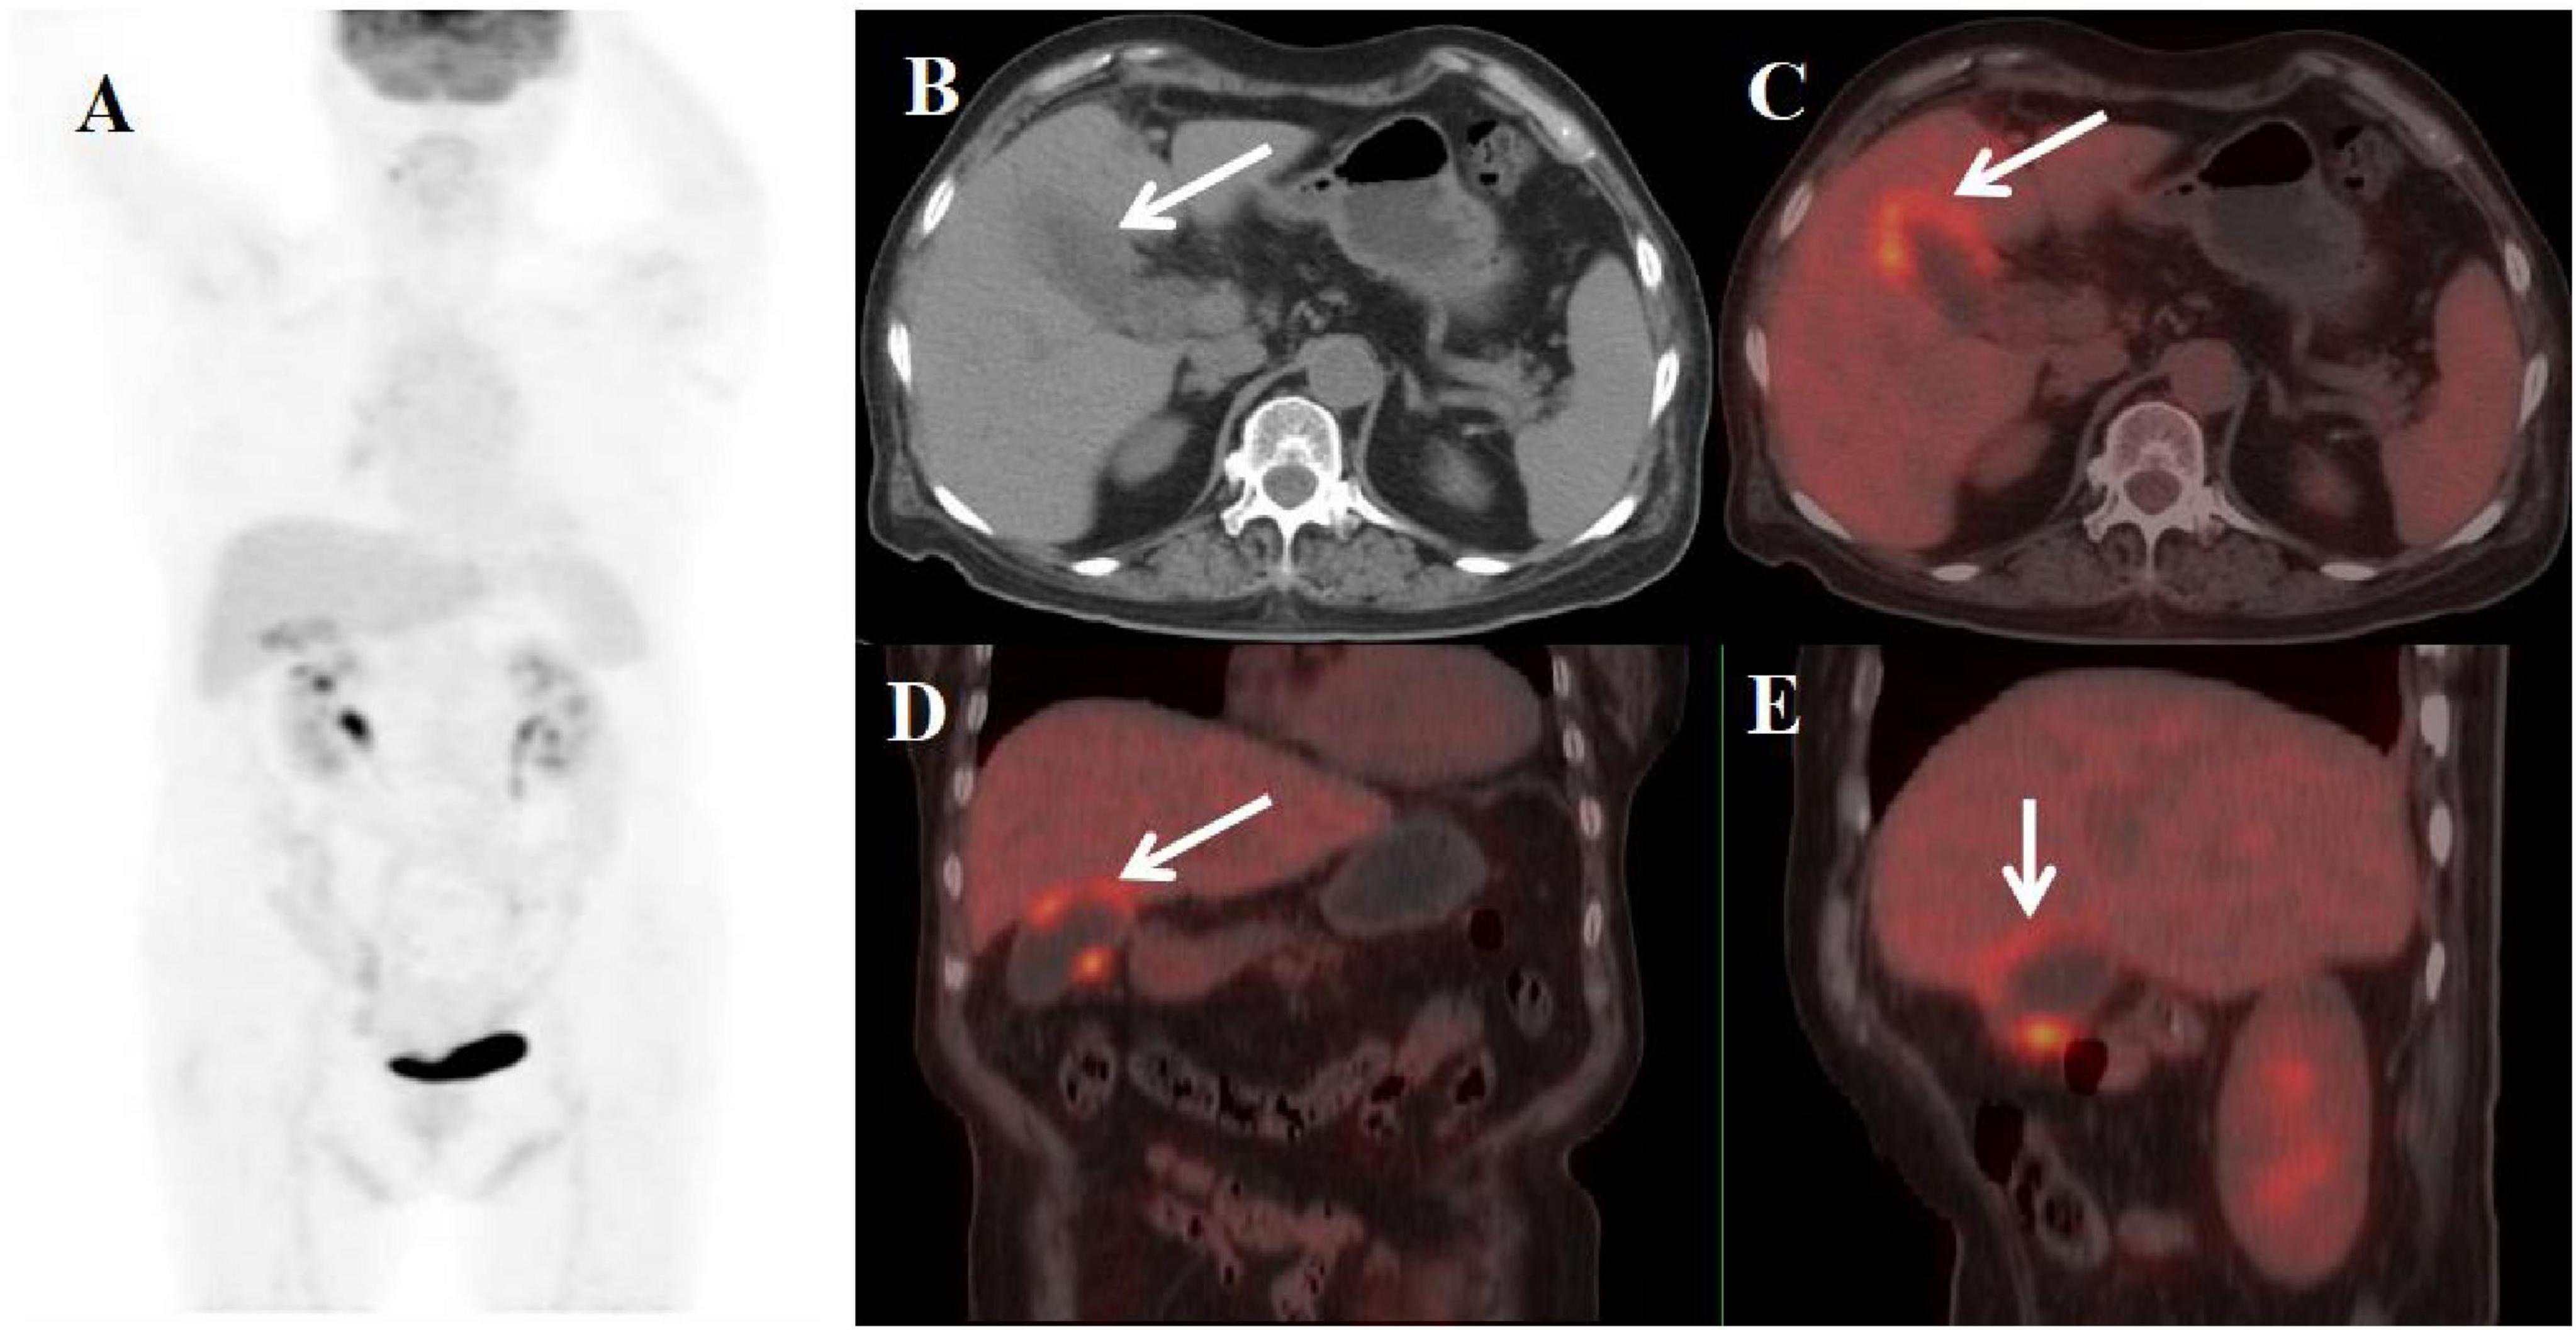

A 70-year-old woman presented with generalized limb weakness persisting for over one month. She had a history of long-standing hypertension (>20 years), recently diagnosed diabetes mellitus (1 year duration), and chronic hypothyroidism (>10 years). Initial laboratory evaluation showed normal white blood cell count (WBC 4.5-10 × 109/L), neutrophil percentage (40–75%), and C-reactive protein level (CRP < 5 mg/L), but demonstrated markedly elevated tumor markers: carbohydrate antigen 19-9 (CA19-9 362.00 U/mL; reference < 27) and carbohydrate antigen 125 (CA125 130.00 U/mL; reference < 35). The patient was subsequently referred for PET/CT evaluation, which demonstrated: (1) gallbladder enlargement with focal wall thickening (maximum 12 mm), (2) preserved mucosal continuity, (3) clear liver-gallbladder interface, and (4) focally increased FDG uptake (SUVmax 5.8) (Figure 4). Following laparoscopic cholecystectomy, histopathological examination confirmed XGC, characterized by foamy histiocyte infiltration and chronic inflammatory changes.

Figure 4. Female, 70 years old. (A) (whole body MIP), (B, C) (Axial CT and fused axial PET-CT), (D) (Fused coronal PET-CT), and (E) (Fused sagittal PET-CT). 18F-FDG PET/CT Imaging Findings: The gallbladder demonstrates focal mural thickening (maximum 12 mm) with overall enlargement (B, C, arrow ↑), while maintaining mucosal integrity and a distinct hepatobiliary interface. These morphological changes are accompanied by localized FDG avidity (SUVmax 5.8) (D, E, arrow ↑).